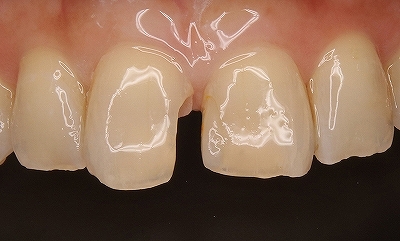

2025 EEdental YAH (7).jpg

今の私は分割面をいかに滑沢に仕上げるか(抜歯のカット面含め)、またこの分割ラインにはマージンは付けていません。

側面(写真の設定を間違え見にくくてすみません^^;)